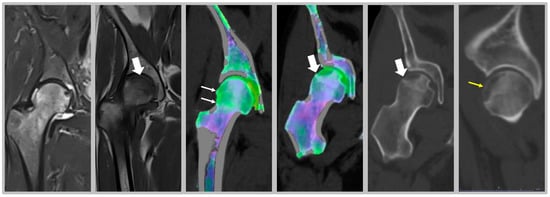

- Hickle, J.; Walstra, F.; Duggan, P.; Ouellette, H.; Munk, P.; Mallinson, P. Dual-energy CT characterization of winter sports injuries. Br. J. Radiol. 2020, 93, 20190620. [Google Scholar] [CrossRef]

- Suh, C.H.; Yun, S.J.; Jin, W.; Lee, S.H.; Park, S.Y.; Ryu, C.-W. Diagnostic performance of dual-energy CT for the detection of bone marrow oedema: A systematic review and meta-analysis. Eur. Radiol. 2018, 28, 4182–4194. [Google Scholar] [CrossRef] [PubMed]